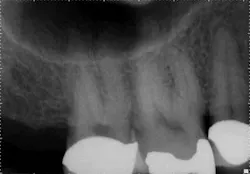

For example, in canal anatomy that appears to be fairly straight on preoperative radiographs in roots with traditional taper, a single file system such as WaveOne(Dentsply Tulsa Dental Specialties) would be an excellent choice to achieve cleanliness and shape (Figs. 1 and 2). The single-file reciprocating system would also have the added benefits of simplicity and efficiency.

In these three cases, different instrumentation systems were used to create the final shape of the root canal system. In spite of differences in the number of files used, the file design and file movement, the end results look very similar. Although potentially confusing to clinicians, the advances in metallurgy and file design allow for safer and more efficient cleaning and shaping of the root canal system than ever before. However, despite these advances, the success rates of endodontic treatment have stagnated over the last several decades, indicating there is more to clinical success than a dense, white line on a radiograph. Canal shaping is important, but it is paramount that an effective irrigation protocol is incorporated into the endodontic procedure to safely and effectively eliminate all possible bacteria.Fig. 1: Although access is usually an issue when treating second molars, the shape of the roots and good chamber size suggest WaveOne would be an ideal file system for tooth No. 2.

Fig. 2: Following establishment of a glide path and removing the dentin triangle, a single WaveOne primary file was used to create the final shape. This shape would allow for deep and safe delivery of irrigants and maximum disruption of biofilm.